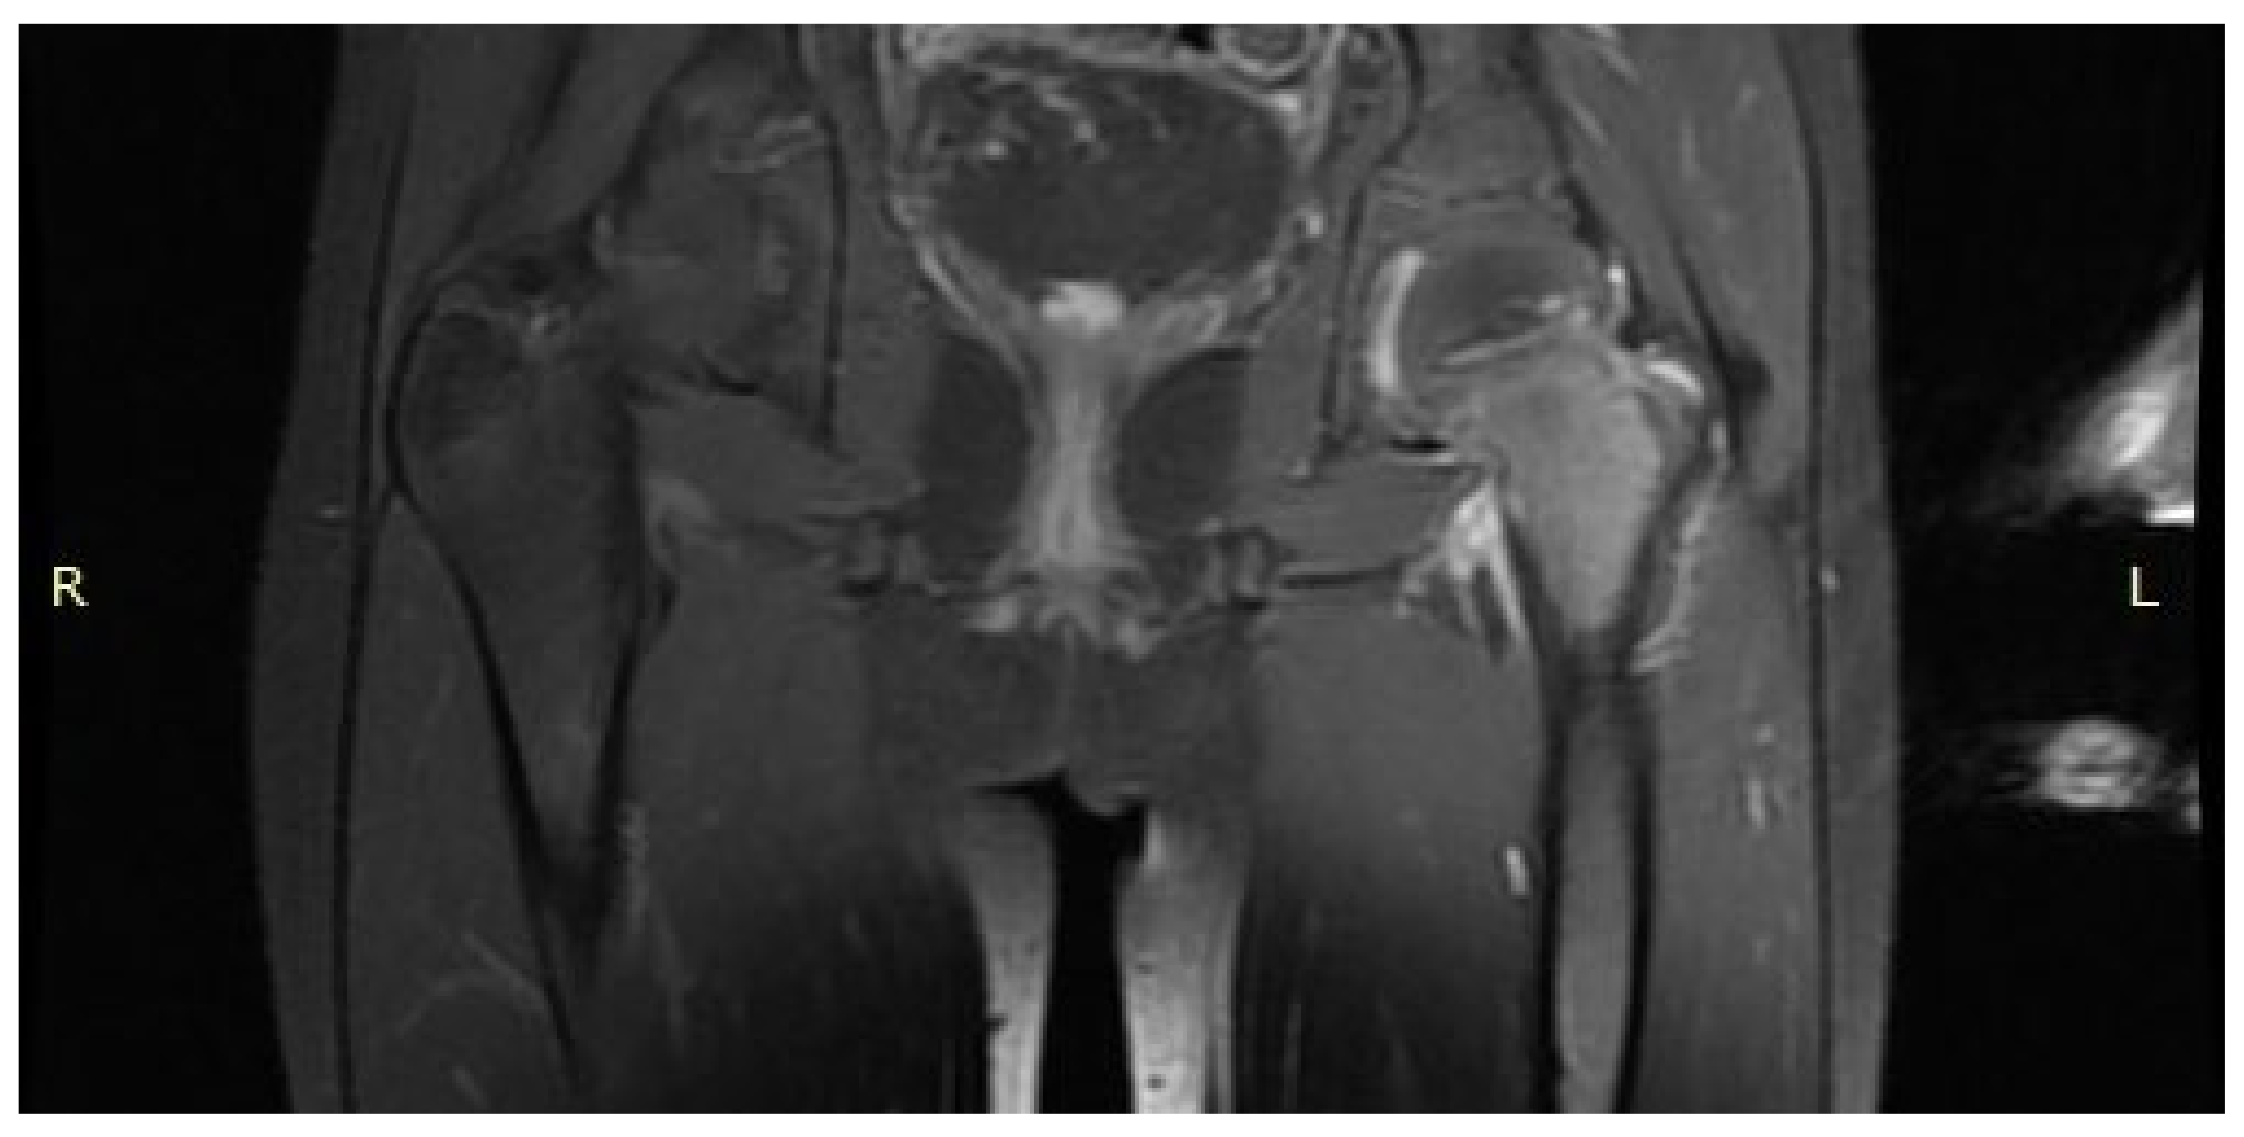

A 14-year-old female patient presented with a history of two years of pain in the left hip with a limp in her leg. The pain occurred mainly at night, waking her from her sleep. The girl associated the onset of her symptoms with an injury. The patient gave a history of a prolonged diagnostic process: 12 hospitalisations, four MRI scans, and numerous X-ray and ultrasound examinations. In the results provided, the first MRI scan already showed a small lesion in the left femoral neck, which was not described in the interpretation of the MRI scans (Figure 12). Based on the MRI scan with the description of bone marrow oedema and the features of synovitis, the patient was admitted to the Paediatrics Department with suspected hip arthritis, treated with antibiotic therapy. Six months later, during another hospitalisation for suspected hip arthritis, laboratory tests showed HLA-B27 antigen, weakly positive antinuclear antibodies, and a positive tuberculin test. The patient was urgently hospitalised at the Lung and Tuberculosis Centre with a diagnosis of latent tuberculosis. With suspected tuberculous hip arthritis, a cortical and synovial biopsy was performed. Treatment with isoniazid for 9 months was administered. Synovitis was present in the biopsy specimen. During a subsequent hospitalisation in the Developmental Age Rheumatology Department, juvenile idiopathic arthritis was diagnosed, and HLA-B27 antigen was detected. The patient was started on methotrexate. At subsequent hospitalisations, treatment with chloroquine and sulfasalazine was started, maintaining treatment with methotrexate. With no signs of improvement, the patient was qualified for biological therapy. In the meantime, a suspicion of femoroacetabular impingement was raised during a series of additional examinations. After almost two years of incorrect diagnosis and treatment, a CT scan of the left hip joint was performed for the first time. The image revealed an osteolytic lesion of 7 × 7 × 6 mm (Figure 13). The description showed the features typical of OO. The patient was qualified for thermoablation with intraoperative 3D navigation. On the day of surgery, the patient presented the limitation of mobility of the left hip joint with VAS 8 hip pain. The day after surgery, the VAS score was 3. On examination 2 months after surgery, there was complete resolution of pain with full mobility of the left hip joint.

Figure 12.

First MRI scan of the hip joints with visible focus of OO (arrow) in the femoral head/neck border, unnoticed.

Figure 13.

CT scan showing a focus of OO (arrow) in the left femoral head.